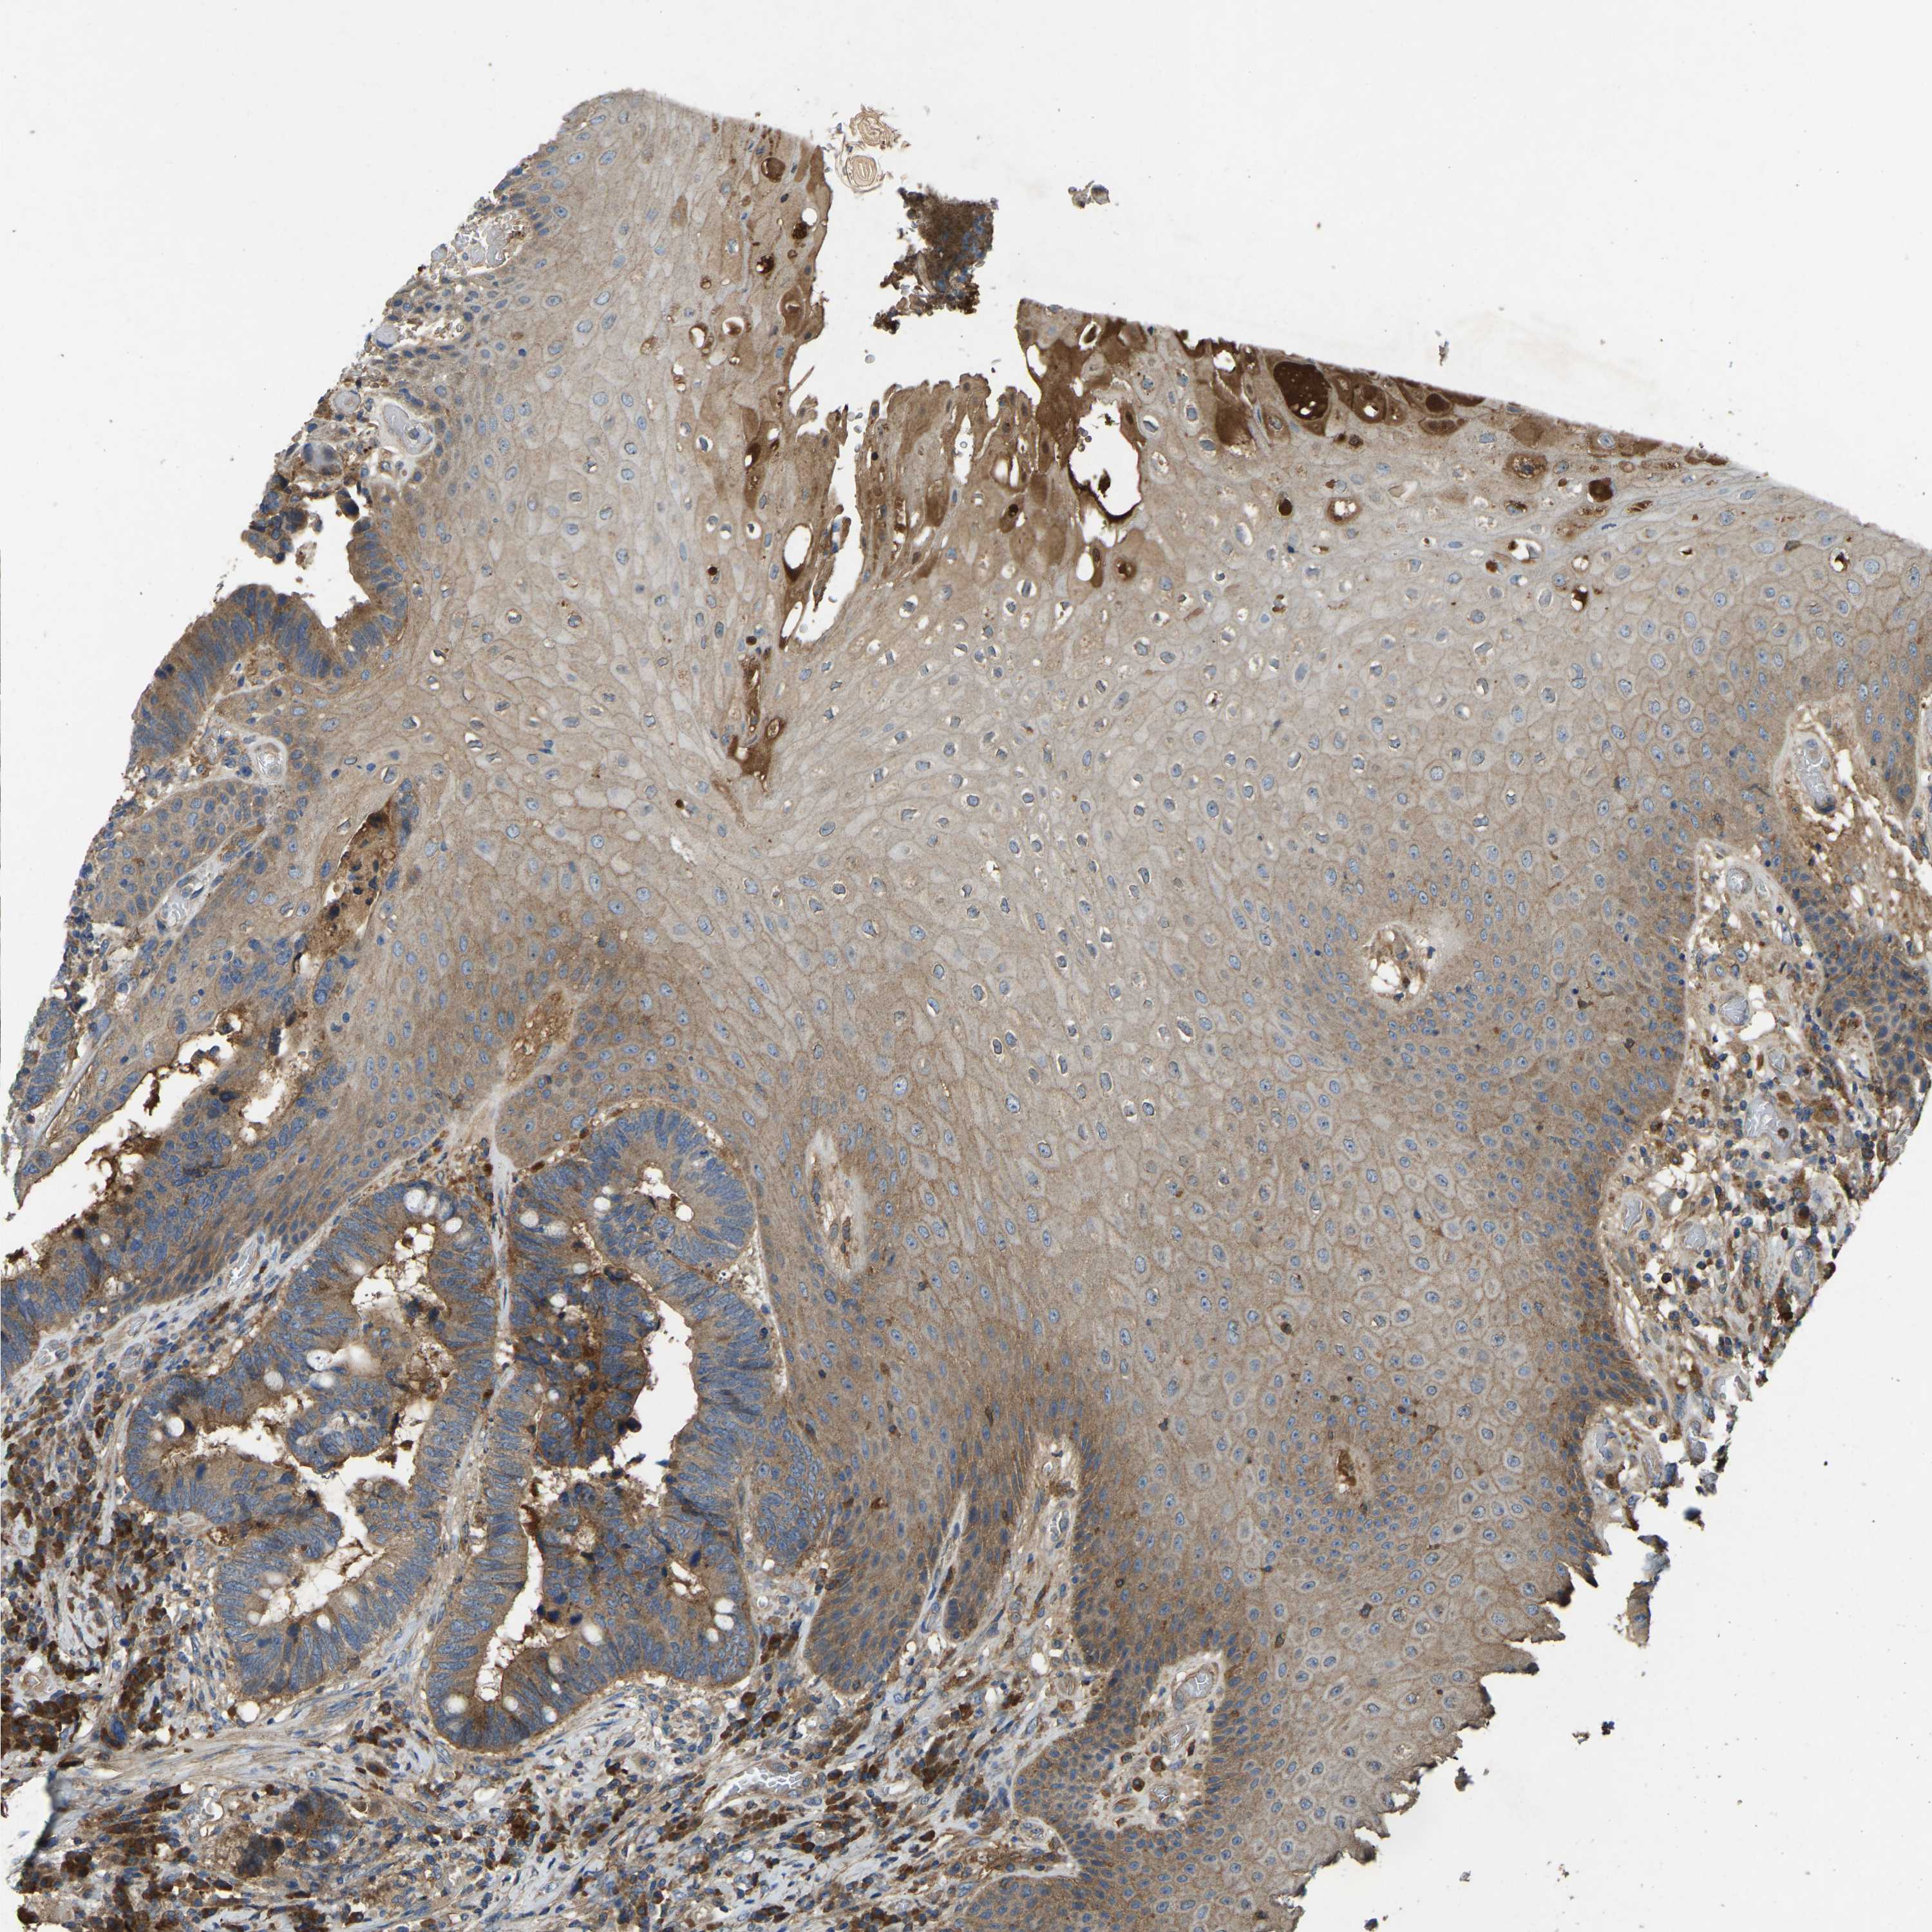

CANCER COLORECTAL CANCER Show tissue menu

Colorectal cancer

Human cancer

Colon adenocarcinoma